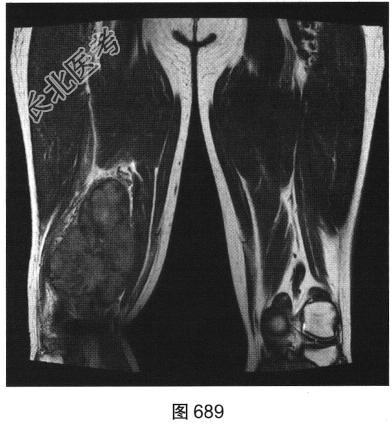

- 多项选择题3.[提示]为进一步明确诊断,患者进一步行CT及MRI检查, 如图686~图691所示。患者CT及MRI的阳性影像表现有( )

A、T2压脂序列上肿块内可见条状高信号

B、右大腿后方肌群内见肿块影

C、T1WI及T2WI均表现为实性肿块,均以等信号为主

D、T2压脂序列呈高信号,周围见明显水肿信号

E、肿块边界较清,密度较均匀

F、肿块周围肌间隙清晰,邻近组织呈受压改变

G、T2WI上可见斑片状稍高信号及低信号分隔

关注下方微信公众号,搜题查看答案